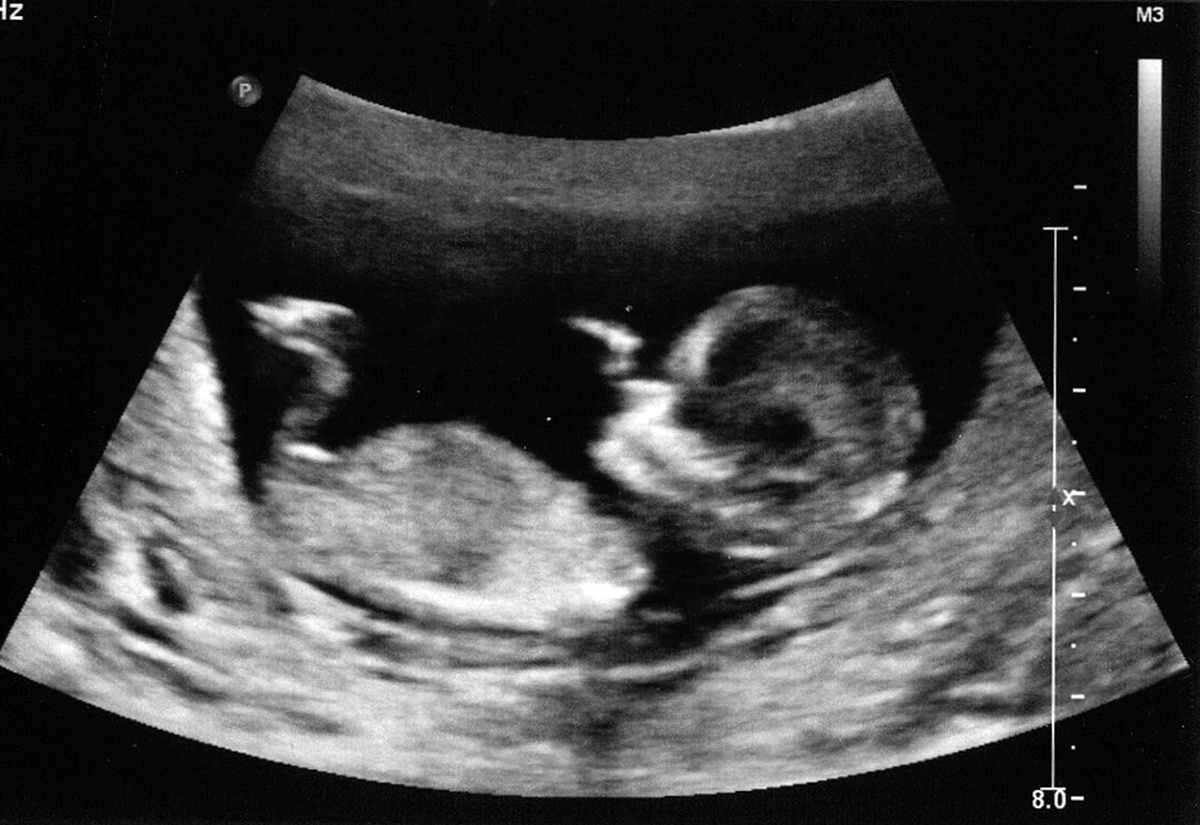

Как проводится сама процедура, кратко - под контролем УЗИ тонкой иглой прокалывается стенка влагалища и стенка яичника, фолликулы собираются и передаются для исследования биологам и эмбриологам в лабораторию.

5) Перенос эмбриона (нов). Самый волнительный и самый приятный день. А здесь от Вас необходим максимально позитивный настрой. Сама процедура длится буквально 10 минут. Под контролем УЗИ Вам переносят в матку Ваш эмбрион, после чего обязательно исследуют под микроскопом катетер с целью утверждения, что эмбриона (нов) в нем не осталось. Ваше маковое зернышко показывают Вам через монитор УЗИ уже внутри Вас. И отпускают домой. Оставшиеся эмбрионы Вы можете заморозить (составить договор и оплатить их содержание) для повторного ЭКО, если оно вдруг понадобится.